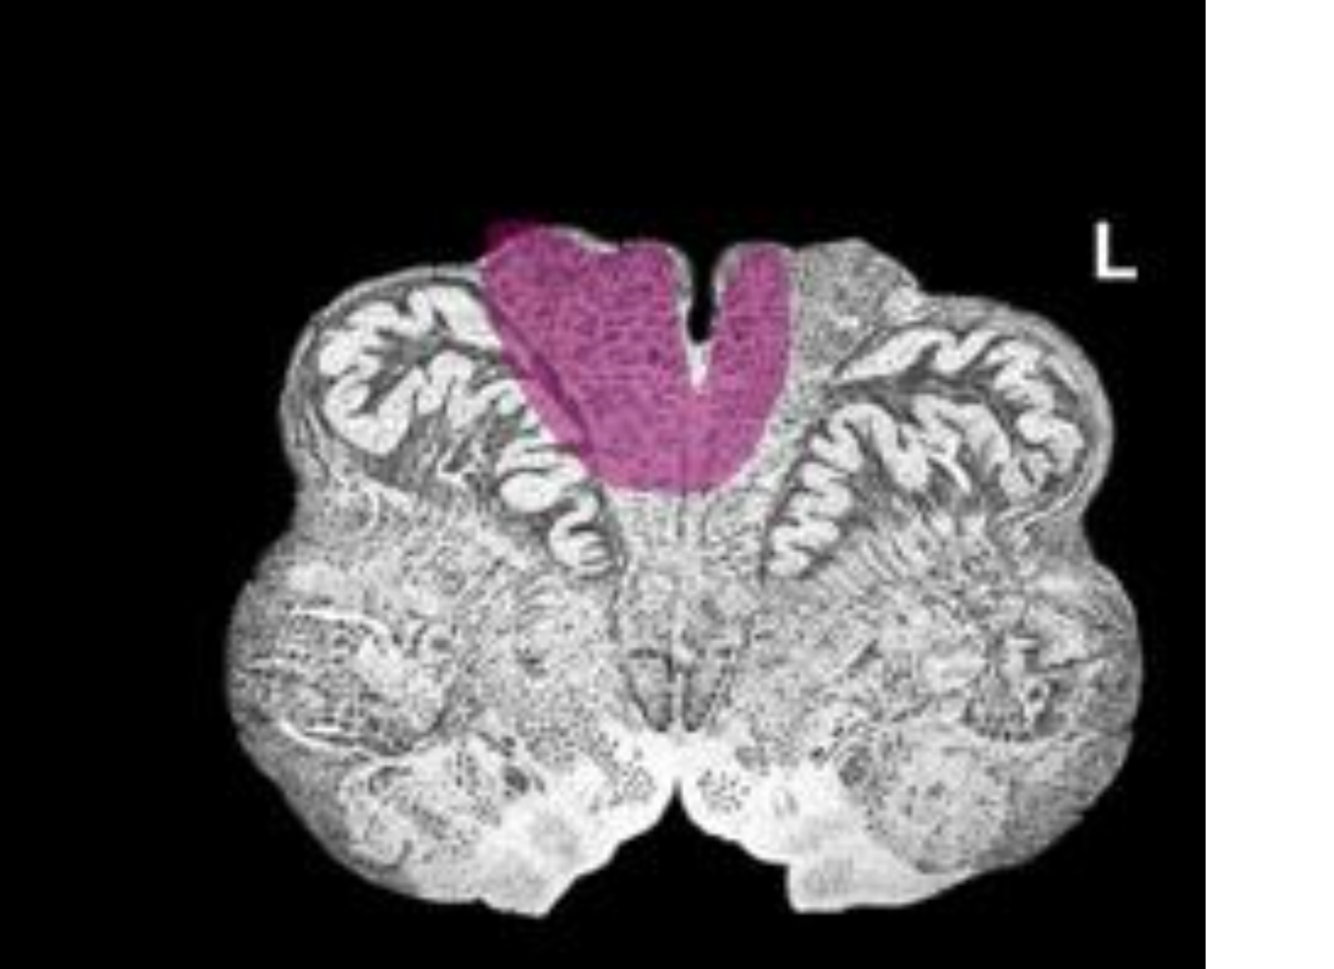

What is the name/location/results of the condition caused by a lesion in the shaded area?

Medulla, mid olive.

Alternating hypoglossal hemiplegia with destruction of contralateral CST

1) Destruction of the hypoglossal nerve results in ipsilateral paralysis and atrophy of the tongue muscles

2) Destruction of the ipsilateral corticospinal tract results in contralateral spastic hemiplegia

3) Partial destruction of the contralateral corticospinal tract results in some degree of ipsilateral spastic paralysis

paralysis and atrophy of the tongue muscles

tongue deviated to right

some L side spastic hemiplegia

complete R side spastic paralysis

lesion is in the rostral medulla, across both pyramids